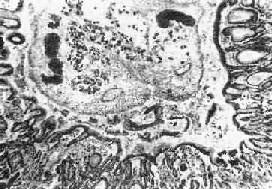

图19-13 肝华支睾吸虫病

胆管内可见虫体,胆管粘膜有腺瘤样增生及炎症

1.肝 肉眼观,肝轻度肿大,尤以左叶为著,严重时在左叶被膜下即可见到因成虫机械阻塞而扩张的胆管分支,可能因左叶胆管较平直,易被童虫侵入之故。切面见肝内大、中胆管呈不同程度扩张和管壁增厚,胆管的直径可达3~6mm,壁可厚达0.5~3mm(图19-12)。胆管腔内充满胆汁,并含有数目不等的成虫。华支睾吸虫前端较细,后端钝圆,形似葵瓜子,虫体长约10~25mm,宽约3~5mm,柔软而半透明。在有大量虫体寄生的病例,解剖时轻压肝脏,即可见成虫由各胆管中鱼贯而出。镜下,根据感染虫数和感染持续时间的不同,病变可轻重不等。肝内胆管扩和,胆管上皮细胞呈不同程度增生,严重者上皮向管腔内呈乳头状增生,并可在粘膜下见多量的增生腺体,形成腺瘤样结构(图19-13)。上皮细胞还常发生杯状细胞化生而分泌大量粘液。管壁有不等量淋巴细胞、浆细胞和嗜酸性粒细胞浸润。慢性病例则伴有明显的纤维结缔组织增生。部分病例汇管区的结缔组织也呈轻度增生,伴有上述炎性细胞浸润。在急性反应时汇管区的小胆管周围也可有多量嗜酸性粒细胞浸润,而肝实质细胞一般无明显改变。